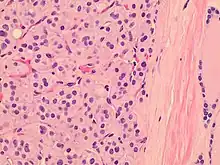

| Histopathology of a Hürthle cell adenoma | |

Hürthle cells are characterized as enlarged epithelial cells. These cells, when stained with hematoxylin-eosin show as pink. This is due to the abundant mitochondria and granular eosinophilic matter within the cells' cytoplasm. These cells are often found in the thyroid. The thyroid is a butterfly-shaped organ, responsible for producing various hormones for metabolism. These cells are often benign, but they can be malignant and metastasize. Hürthle cells are resistant to radiation, but can be treated using radioactive iodine treatment.[4]